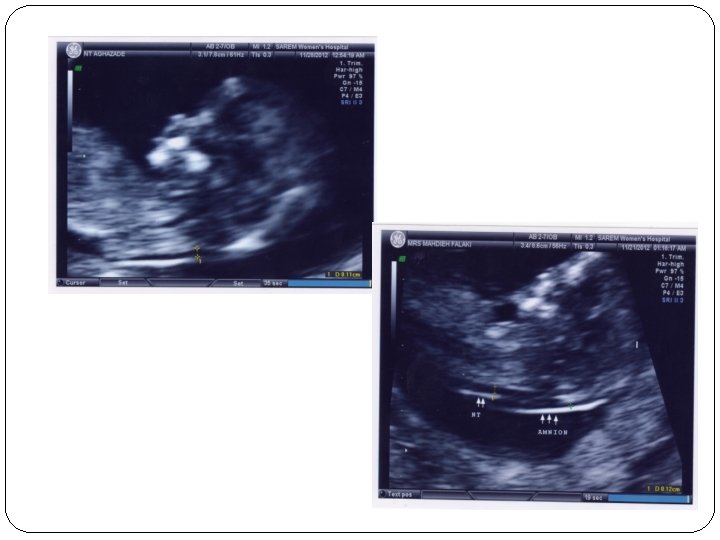

CRL measurement � CRL measurements can be carried out transabdominally or transvaginally. � A midline sagittal section of the whole embryo or fetus should be obtained. � An image should be magnified sufficiently to fill most of the width of the ultrasound screen, so that the measurement line between crown and rump is at about 90 ◦ to the ultrasound beam. � The end points of crown and rump should be defined clearly. � Amniotic fluid should be visible between the fetal chin and chest

� 1 -Mid-sagittal section � 2 -Neutral position � 3 -Horizontal orientation � 4 -Crown and rump clearly visible � 5 -Correct caliper placement � 6 -Good magnification � 1 -Midline facial profile, fetal spine and rump should all be visible in one complete image � 2 -There should be fluid visible between the chin and the chest of the fetus and the ‘profile line’* should form an acute angle with the CRL line before the rump � 3 -Fetus should be horizontal with line connecting crown and rump positioned between 75 ◦ and 105 ◦ (90± 15) To ultrasound beam � 5 -Intersection of calipers should be on outer border of skin covering skull and outer border of skin covering rump � 6 -Fetus should fill more than two-thirds of image, clearly showing crown and rump

NT measurement - CRL: 45 -84 mm (11 w-13 w 6 d) - TAS(95% success)=TVS(other 5%) - Good sagital section. neutral position(hyper ext: 0. 6 mm hyper flex: 0. 4 mm) - Magnification : fetus ¾ image - cine each incremental distance: 0. 1 mm - Waiting for spontaneous fetal movement, asking the mother to cough, tapping the maternal abdomen(amnion membrane!)

NT measurement - More than one measurement and record the maximum one - Good work after 80 -100 sonography and at least 10 min - Study on 100, 000 cases: normal: 1. 2 (11 w) to 1. 9(13 w 6 d) abnormal: above the 95 th centile(>=3 mm)

- Umbilical cord around the fetal neck( 5 -10%): 0. 8 mm different above and below : record the average